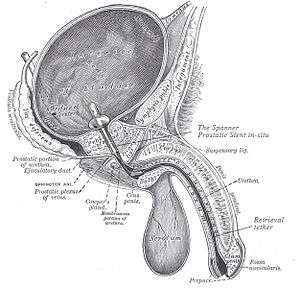

| Prostatic stents are places from the bladder through the prostatic and penile urethra to allow drainage of the bladder through the penis. This is sometimes required in benign prostatic hypertrophy. |  Example of a stent / catheter used in the prostate to treat an enlarged prostate and provide relief in cases of obstructed urination |